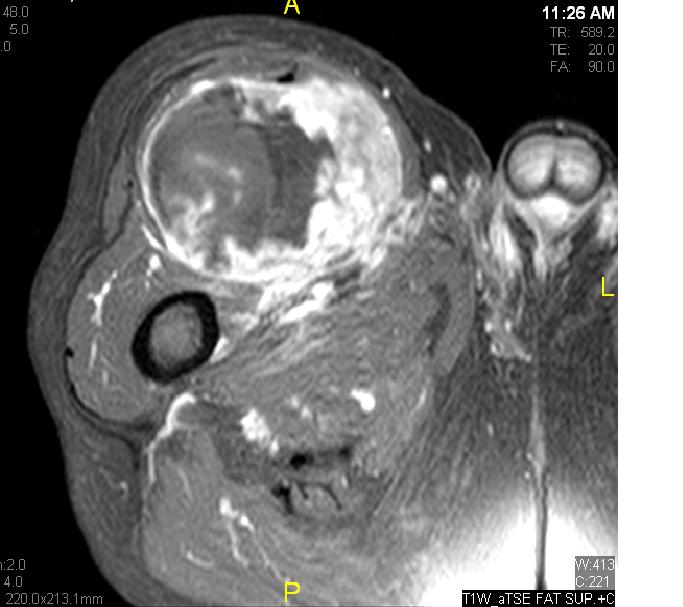

Fig. 7 & 8 Magnetic Resonance Image shows a large heterogeneous mass in the right thigh with low intensity signal on Axial (Fig. 7) and Coronal (Fig. 8) T1-weighted images admixed with high signal areas. The high signal areas represent low grade fatty tissue and low signal the dedifferentiated areas. Higher intensity signal is visible compatible with hemorrhage or necrotic tissue.

Fig. 11 – 13 Axial (Fig. 11), Coronal (Fig. 12) and Sagital (Fig. 13) contrasted T1-weighted MR images show a large heterogeneous mass with central and peripheral

enhancement. Multiple thick trabeculations. Central low signal intensity image is compatible with necrosis and hemorrhage.